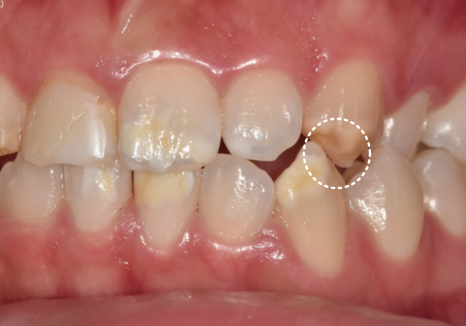

바로 교합,

즉 치아 맞물림 상태였는데요,

확인 결과,

양쪽 송곳니 부위가

긴밀하게 맞물리고 있었고,

씹을 때 힘이 직접적으로

전달되는 구조였습니다.